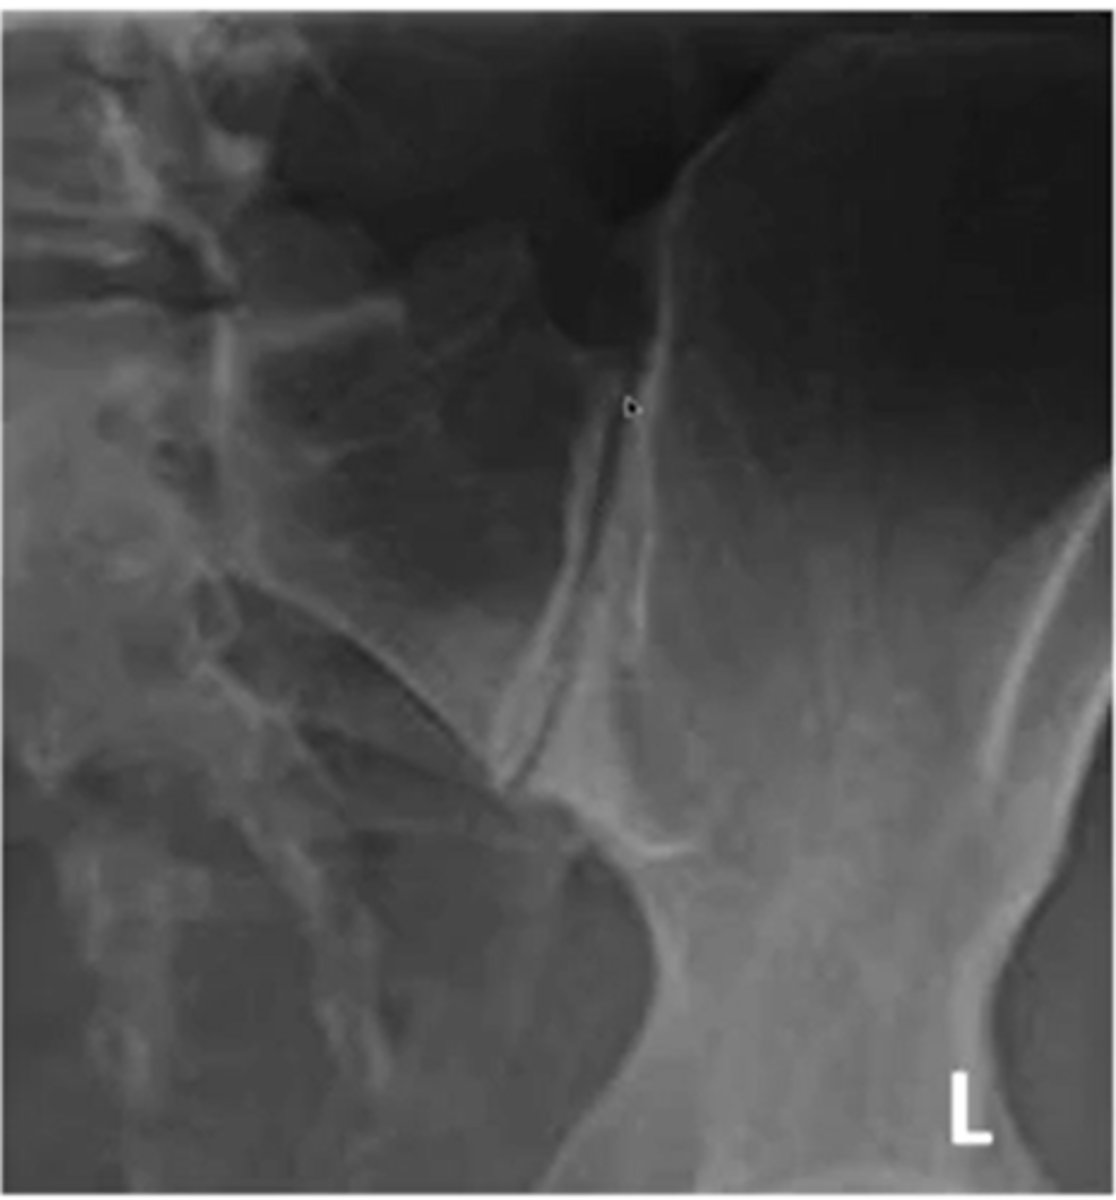

what are the two views of the SIJ

(what are you looking for in each view)

AP (looking at the joint surface)

R/L oblique ( joint space)

when looking at a R oblique of the SIJ what side are you looking at

the left

what kind of angle is the CR shot for an AP SIJ xray

inferior to superior 30-35 degrees

what is an example of an oblique image of the SIJ

for the SIJ would you use a AP or an oblique view for joint space

oblique